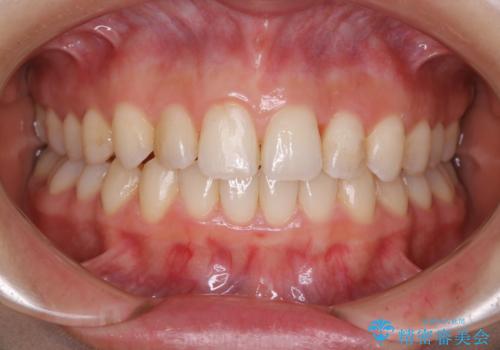

30代女性 前歯のがたつき

![[ 前歯のガタつきを治す ]マウスピース矯正インビザラインの症例 治療後](https://seimitsushinbi.jp/wp/wp-content/uploads/2022/01/IMG_9999-500x350.jpg?v=1642039754)